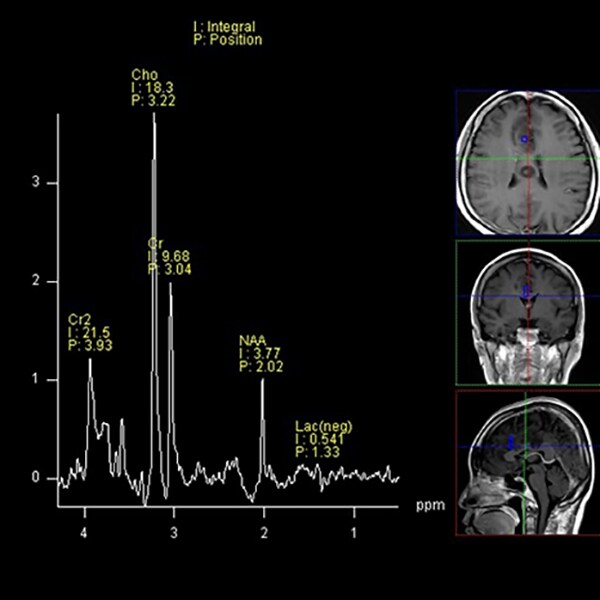

T1WI低信号、T2WI高信号、FLAIR高信号、DWIでやや高信号の腫瘤。Gdで腫瘤は造影されず、DSC-Perfusionでは辺縁~中心部に一部血流の高い部分あり。MRスペクトロスコピーではCho上昇とNAA低下がみられる。Low grade gliomaを疑う。後日、摘出手術が施行され、病理診断はoligodendroglioma NOS(Grade 2)であった。

当該疾患の診断における造影MRIの役割